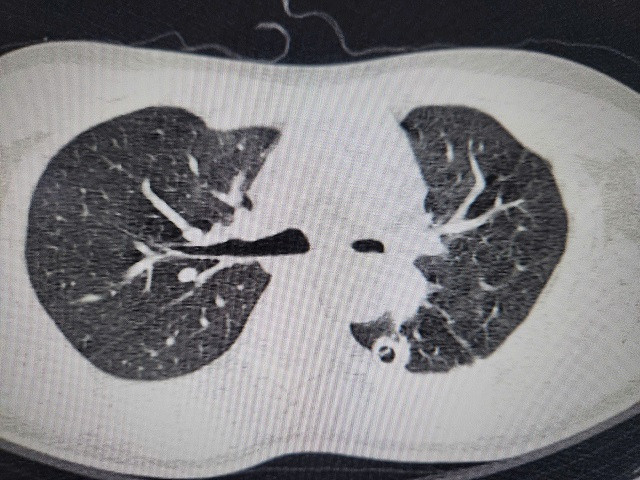

| Hình ảnh phim chụp hẹp phế quản gốc trái, xẹp hoàn toàn phổi trái do di chứng của lao phổi - Ảnh BVCC |

Anh B được chuyển đến Khoa Phẫu thuật Lồng ngực, Bệnh viện Bạch Mai. Qua các thăm khám lâm sàng và chụp chiếu, kết quả quả cho thấy, anh B đối diện với nguy cơ mất phổi vĩnh viễn: Chụp CT 3D phổi cho thấy phế quản gốc trái chỉ còn khe hẹp 2mm, phổi xẹp đặc như tấm bìa cứng. Nếu không phẫu thuật trong 2 tuần, phổi sẽ hoại tử.